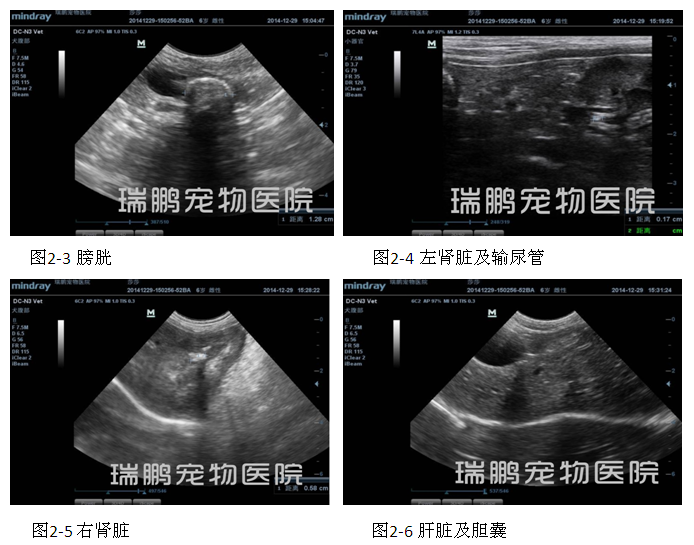

输尿管、膀胱切开取石术后3天,对患犬进行泌尿系统超声波检查,其结果显示膀胱内有尿液充盈,膀胱壁轻微增厚,凹凸不齐,未见明显的高回音性结石团块残留(图4-1);左肾盂仍然轻微扩张,肾脏长轴大小为3.92 cm(图4-2);肾门附近的输尿管通畅良好,管腔内未见明显异常的影像(图4-3);膀胱附近(原来输尿管结石部位)的输尿管通畅,无明显的异常影像(图4-4);右肾盂内仍然有高回音性影像,提示肾结石仍然存在,结石直径大小约为0.53 cm,肾脏皮髓质层交界模糊不清,肾脏轮廓不清晰(图4-5)。